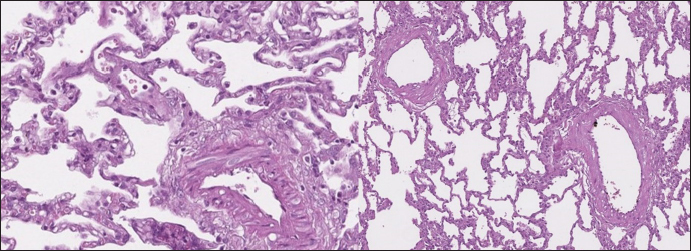

In dogs with RHF, with both Masson’s trichrome and hematoxylin and eosin staining, we found wide fields of pulmonary fibrosis, arterial thickening due to tunica media proliferation, and plexiform vascular lesions with signs of revascularization. The dog with pneumonitis showed chronic interstitial histiocytic pneumonia (Fig. 3).

Fig. 3. RHF group. Left top—aggressive lung remodeling, resembling organizing diffuse alveolar damage with collapse and fusion of the alveoli and loss of typical structure. Right top—tunica media and adventitia proliferation around pulmonary vessel. Left bottom—partial occlusion of pulmonary vessel. Right bottom—plexiform vasculopathy with lumen obstruction and revascularization, presented with onion-like structure. Stained with H&E.

Fig. 4. sPCH group. Left (dog)—portions of alveolar septae with duplicated capillaries and capillaries proliferation into arterial walls. Right (cat)—less prominent septal alteration, significant arterial walls capillary proliferation. Stained with H&E.